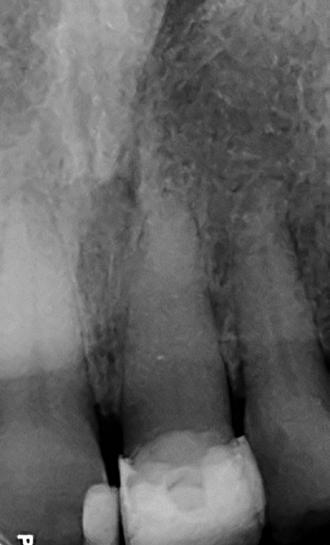

The patient was originally referred concerning this tooth in 2022. A CBCT scan was recommended because the clinical assessment revealed no pathological findings – however, a small lateral lesion was suspected. A periapical x-ray revealed severe calcification of the tooth (Figure 1).

The patient returned in May 2024 reporting a history of slight discomfort

from the tooth. In the intervening two years, the patient’s dentist had applied a composite build-up, secured using two pins, making the UL1 heavily restored. A new CBCT scan showed severe calcification of the root canal, and a lateral radiolucency mid-root on the distal aspect (marked with red arrow) (Figure 2).